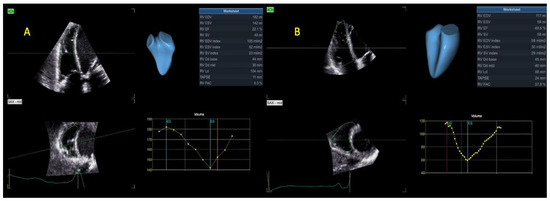

Assessment of the RV

| 3D RVEDV (mL) | 93 ± 47 | 127 ± 59 | 0.01 |

| 3D RVEDV index (mL/m2) | 49 ± 25 | 67 ± 29 | 0.01 |

| 3D RVESV (mL) | 55 ± 35 | 80 ± 44 | 0.01 |

| 3D RVESV index (mL/m2) | 30 ± 19 | 43 ± 21 | 0.01 |

| 3D RVSV (mL) | 38 ± 16 | 47 ± 19 | 0.039 |

| 3D RVSV index (mL/m2) | 20 ± 8 | 25 ± 10 | 0.058 |

| 3D RVEF (%) | 44 ± 10 | 38 ± 8 | 0.03 |